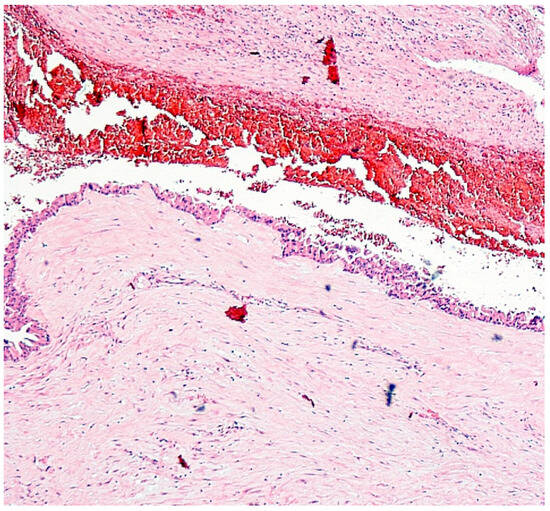

| Feature | Case 1 | Case 2 |

| Patient Demographics | 60-year-old Caucasian male | 28-year-old Caucasian female |

| Clinical Presentation | Incidental discovery of an 8 × 8 × 9 cm hepatic cyst | Presented with dyspnea, vomiting, jaundice, fever |

| Diagnostic Methods | MRI, MRCP, ERCP, histopathological examination | CT, MRI, laparoscopic liver biopsy, histopathological examination |

| Tumor Characteristics | Large cystic mass, thin walls, internal septa, papillary projections, enhancing solid components | Large lesion in left hepatic lobe, hyperintensity in T2-weighted images, restricted diffusion, contrast enhancement |

| Histopathological Findings | IPNB with foci of adenocarcinoma, oncocytic appearance, varying degrees of dysplasia, mucus within cyst | Adenocarcinoma with papillary clear cell and mucinous appearance, gland ectasis, cystic or pseudocystic aspects |